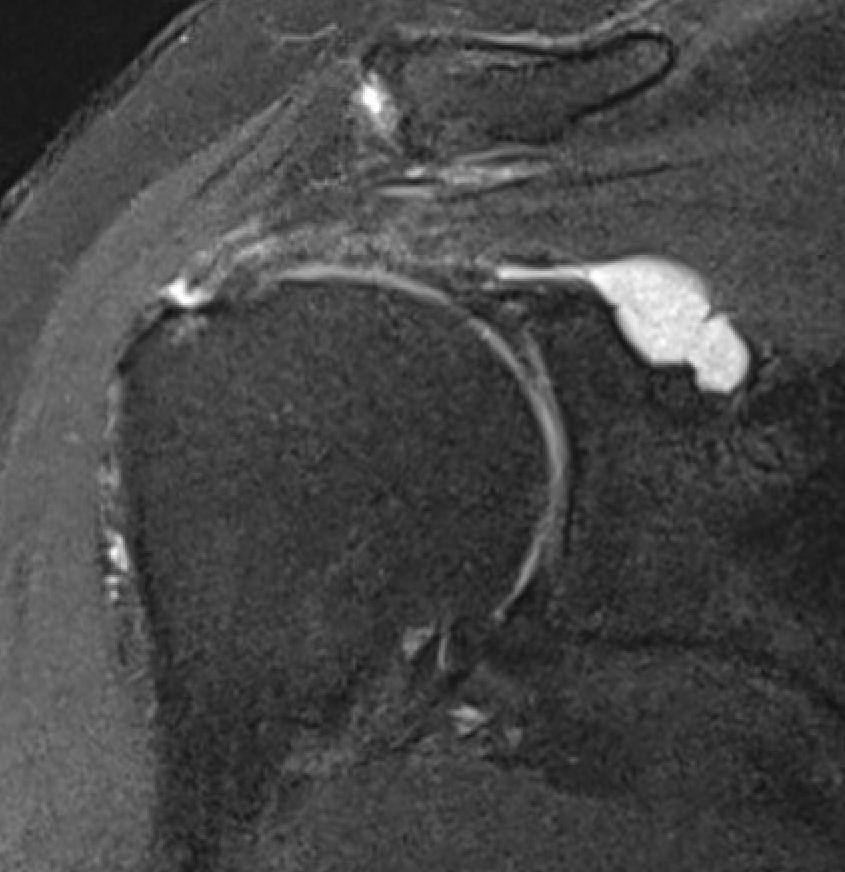

MRI

Spinoglenoid cyst

Spinoglenoid cyst with SLAP tear and posterosuperior labral tear